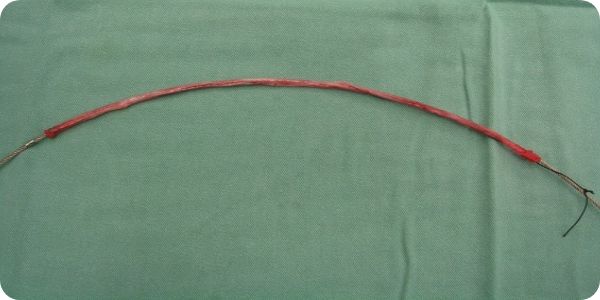

静脈の逆流を止める!

静脈瘤の原因となっていた静脈を抜去